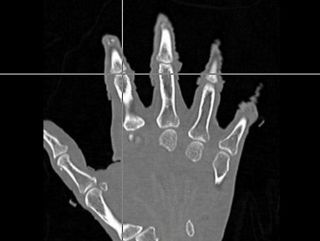

Integrate additional ITK transform types into the neural network using the general ITK transform I/O mechanism. Evaluate the changes to segment the phalanx bones bones of the hand.

- The first was that we have integrated a rigid body initialization for a Thirion Demons registration for atlas <-> subject registration. The above modification was used to warp the atlas to the subject as shown in the figures.